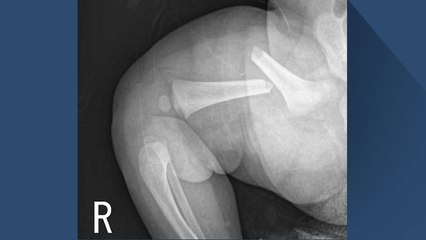

지금 보고 계시는 이 엑스레이 사진. br br 생후 50일 된 여자아기의 허벅지 뼈가 완전히 부러진 모습인데요. br br 사진으로만 봐도 말 못하는 아기가 얼마나 고통스러웠을지 짐작이 갑니다. br br 허벅지 뼈뿐만 아니라 쇄골도 부러진 이 아기, 무슨 사고라도 당한 걸까요? br br 아닙니다. 아이의 친아버지인 A 씨가 한 일이었습니다. br br A 씨는 지난 2016년 5월, 전북 전주 자신의 집에서 생후 50일 된 딸의 허벅지와 쇄골을 부러뜨린 혐의로 재판에 넘겨졌는데요. br br A 씨는 수사를 받을 당시에도 '신생아 체조를 하다 뼈가 부러졌다', '잠결에 딸을 소파에서 떨어뜨렸다'는 등 말을 바꾸며 혐의를 부인해왔습니다. br br 앞서 1심 재판부는 검사가 제출한 증거만으로는 A 씨가 일부러 아이를 다치게 했다는 점이 명확하지 않다며 아동학대 혐의에 대해 무죄를 선고했는데요. br br 하지만 2심 재판부의 판단은 달랐습니다. br br 아이의 뼈는 어른보다 탄성과 유연성이 높아 A 씨의 주장처럼 실수로 골절이 생기긴 어렵다는 법의학 교수의 소견에 더해, br br A 씨가 그동안 결혼과 육아에 스트레스를 받아왔다는 점을 근거로 징역 1년 6개월을 선고하고 법정구속했습니다. br br A 씨는 20대 초반의 나이에 계획에 없던 아이를 가지게 되면서 게임에 몰두하고 우울 증상도 보였던 것으로 조사됐습니다. br br 또 '딸이 안 자서 잠을 못 자 짜증 난다'거나, '딸이 괜히 밉다'는 취지의 메시지를 어머니에게 보내기도 했던 것으로 드러났는데요. br br 생각지도 않게 한 생명의 아버지가 된 상황이 힘들고 짜증 날 순 있지만, 아버지 잘못 만나 끔찍한 고통을 겪은 아이는 도대체 무슨 죄인지, A 씨가 잘 생각해봤으면 하는 바람입니다. br br 앵커 : 김경수 br 자막뉴스 : 육지혜br br ▶ 기사 원문 : ▶ 제보 안내 : , 모바일앱, 8585@ytn.co.